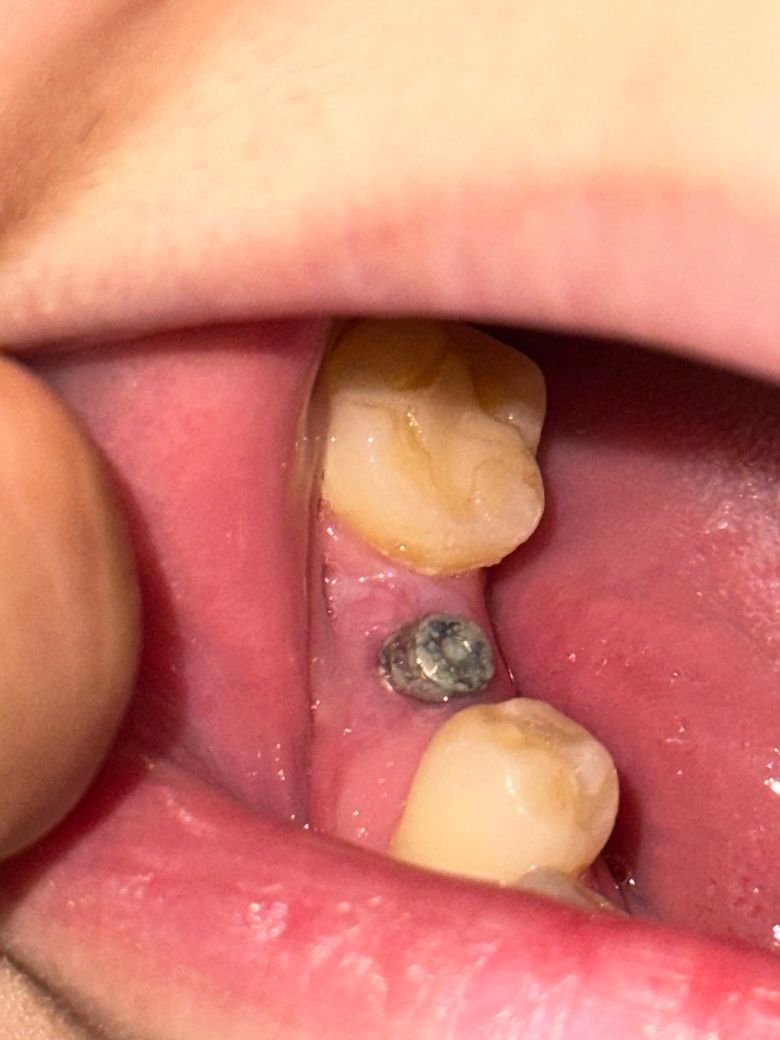

임플란트 나사식립 11일차입니다 올바르게 회복이 되었는지 궁금합니다 ?

임플란트 나사 식립한지 11일차입니다

가글은 7일사용 하라해서 그렇게 했고 이후로 식립된 부분 잇몸 쪽만 살살 양치를 했는데요 나사는 안건드리는게 맞나요 닦아줘야하나요 ? 양치 방법더 궁금하고 잘아물고 있는지도 궁금합니다

• 1번 째 사진

잇몸은 잘 회복된 것 같습니다 해당부위도 위생관리 잘 해주어야 합니다 살살 잇몸, 임플란트 뚜껑 닦아주세요